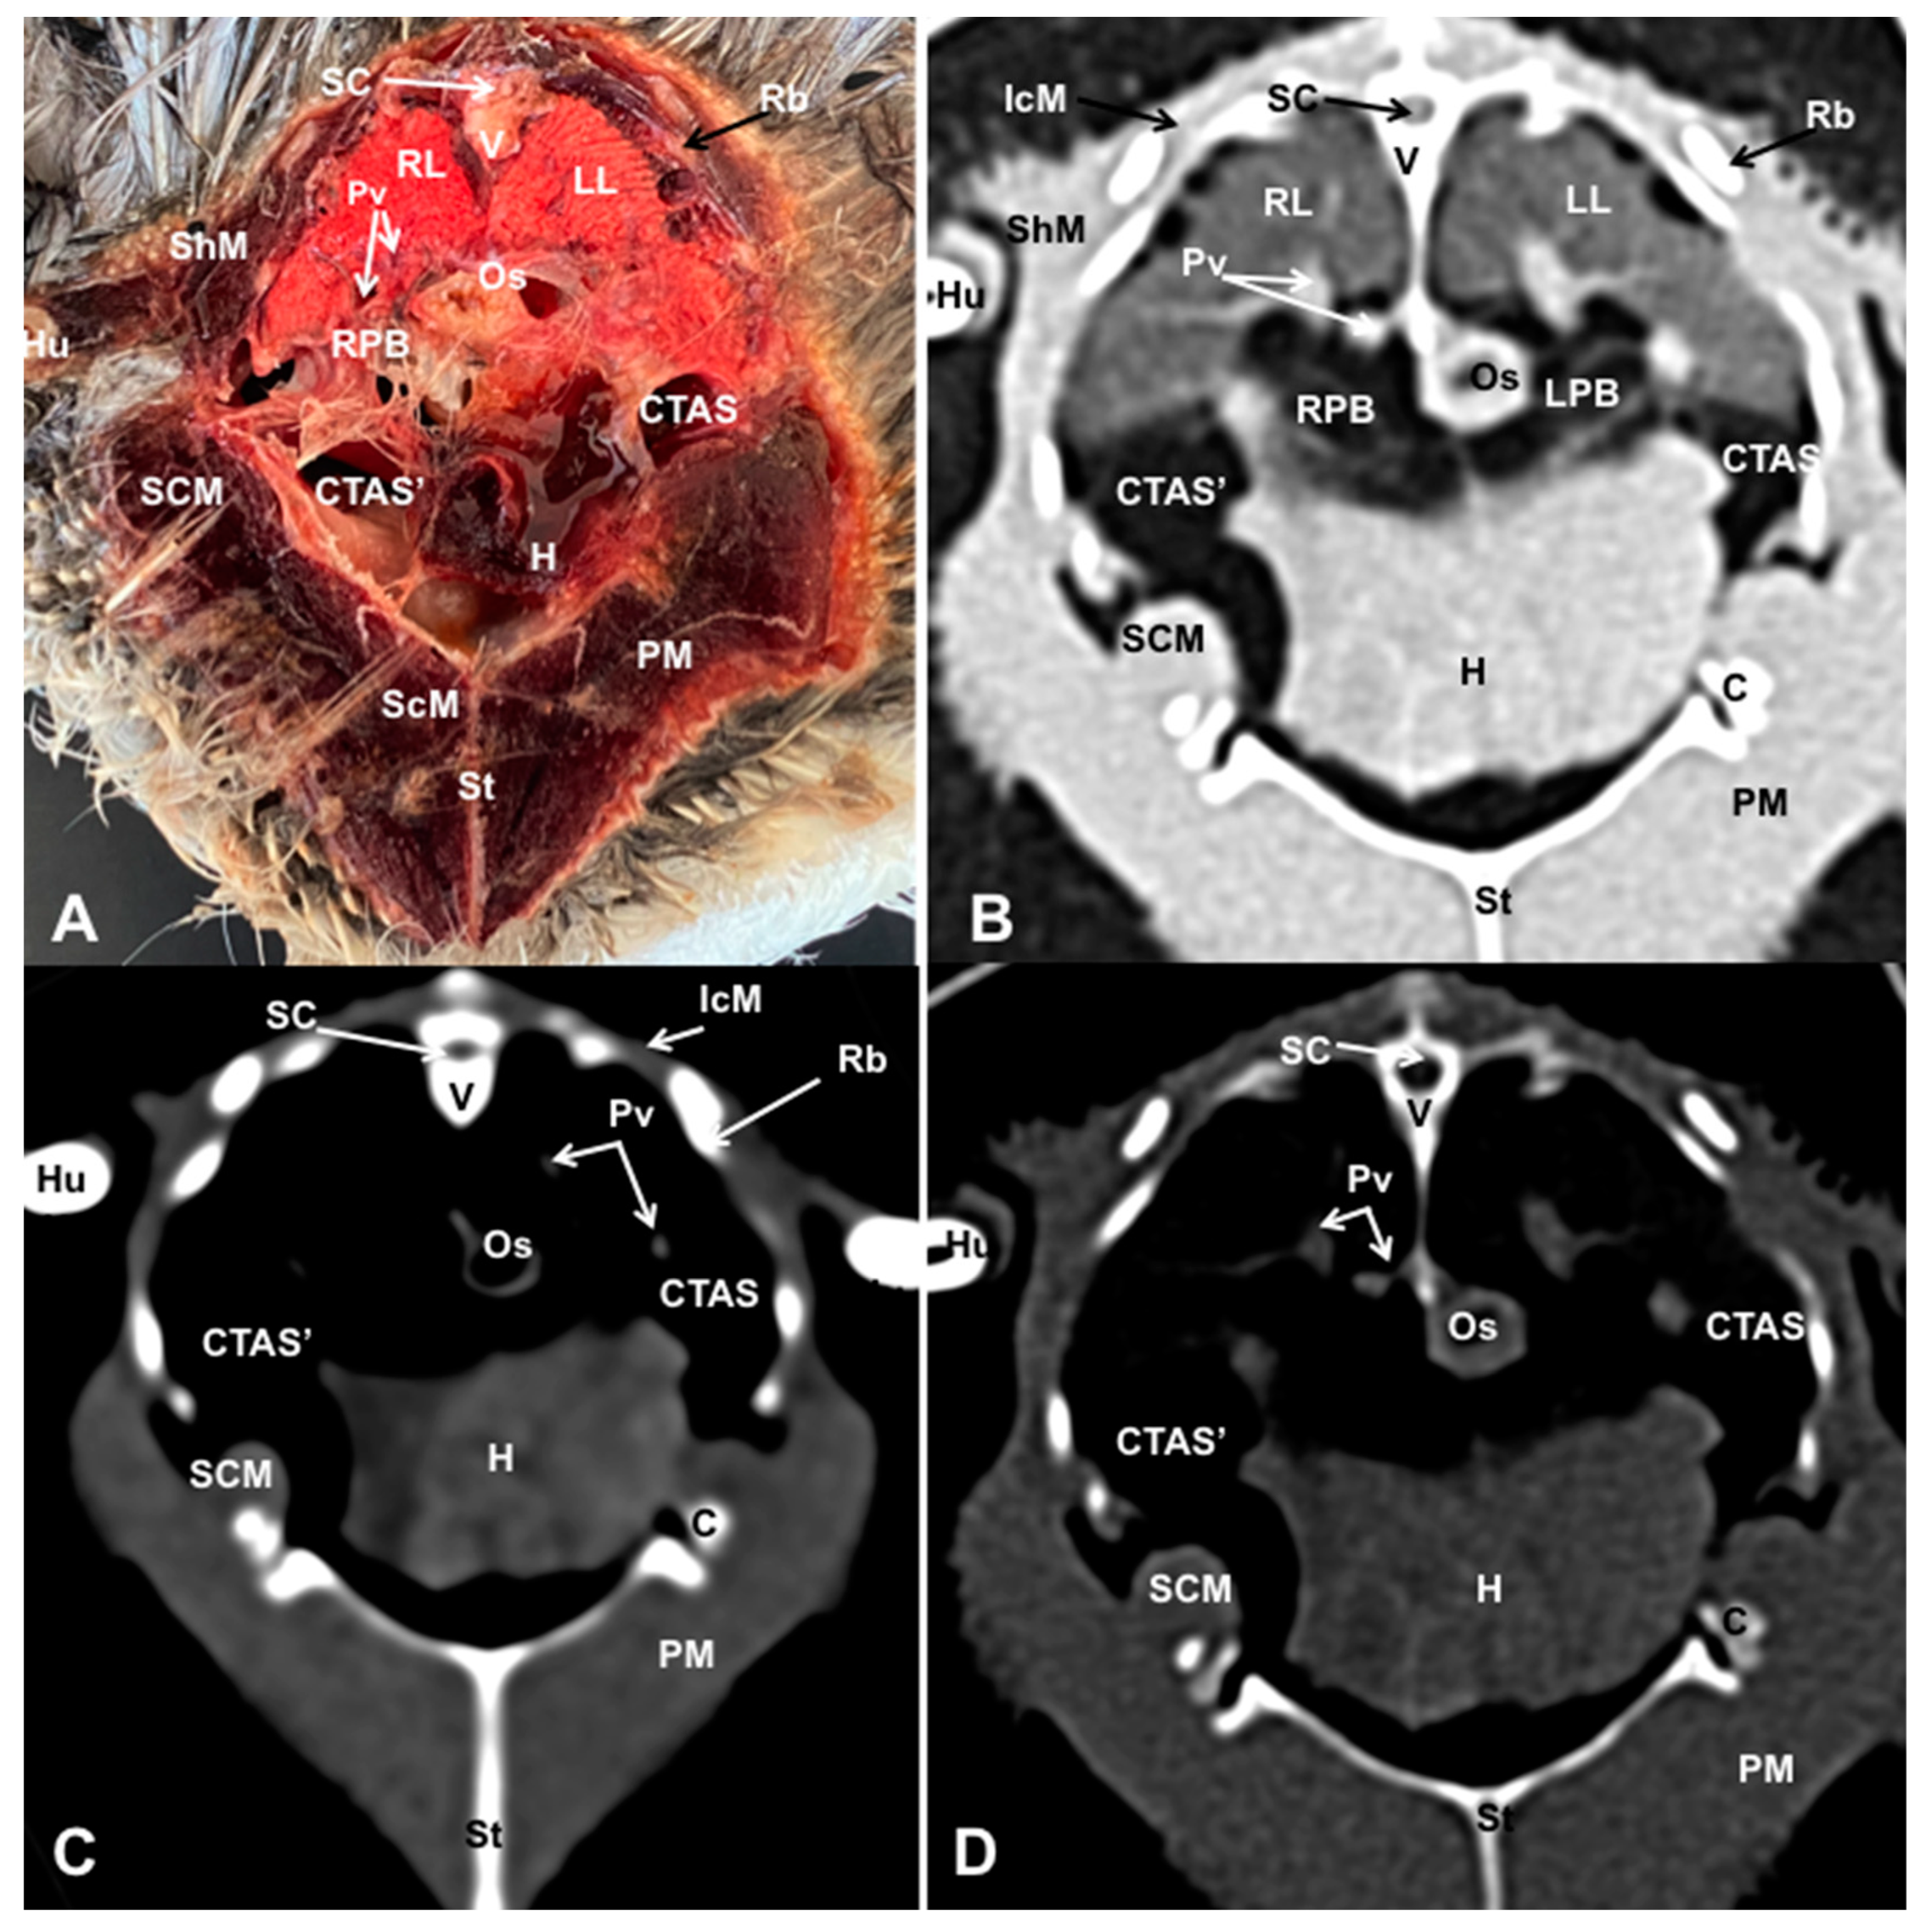

3.1. Anatomical Dissections and Cross-Sections

3.2. Computed Tomography Images